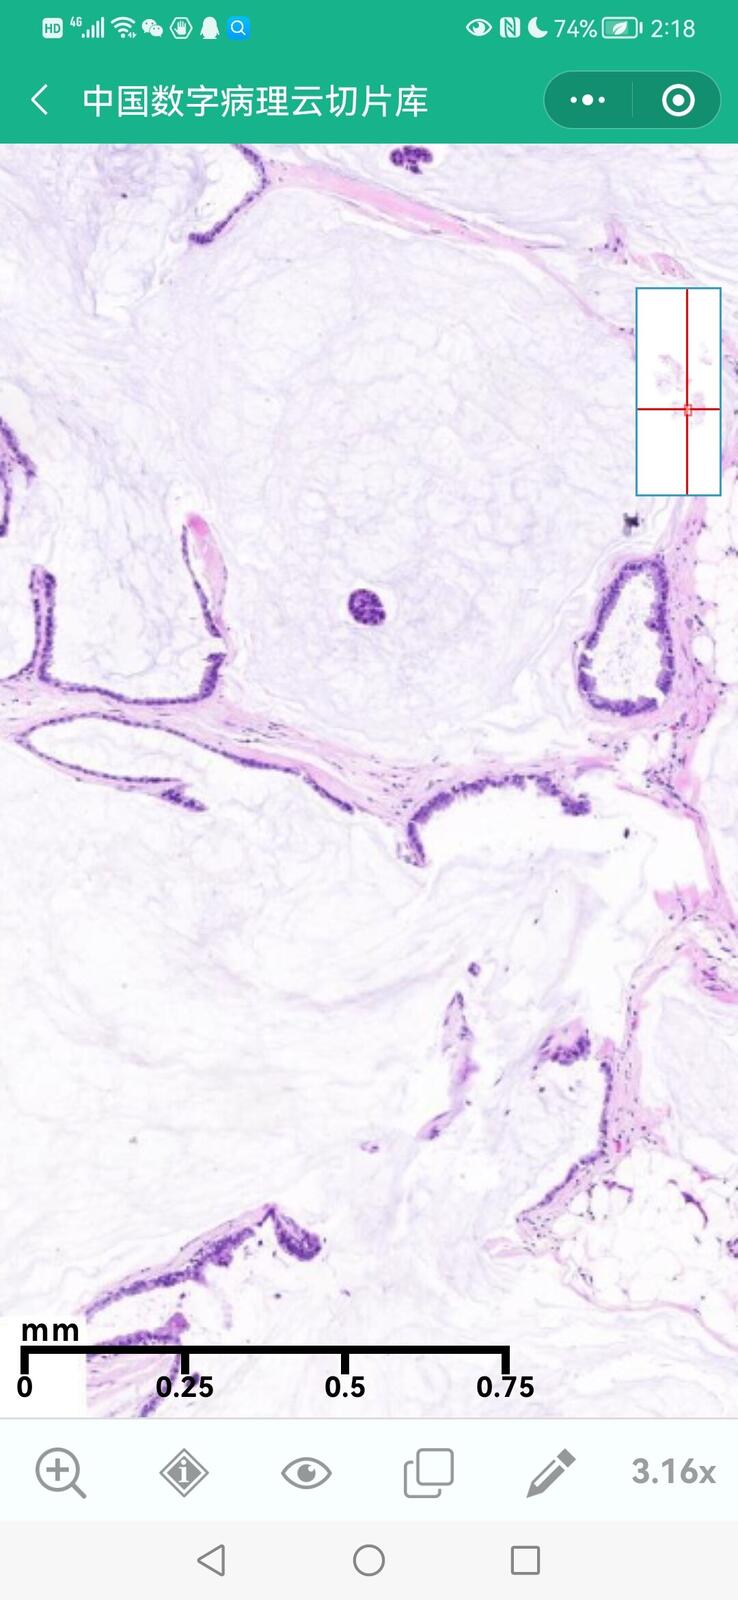

乳腺黏液性囊腺瘤伴导管内癌